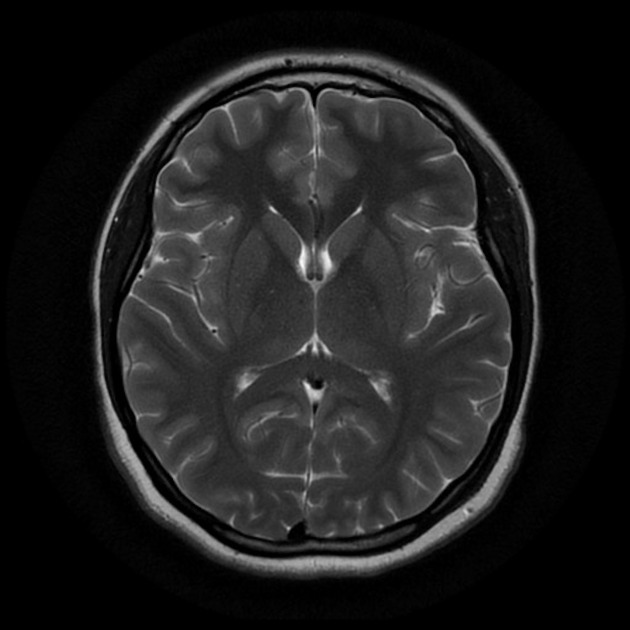

Giới khoa học Trung Quốc đã công bố kế hoạch xây dựng một máy quét não cấp độ khủng khiếp, được đánh giá là mạnh nhất thế giới hiện nay. Máy này có khả năng tích tụ từ trường cực mạnh, giúp lần đầu tiên trong lịch sử dựng lại hoạt động của toàn bộ các neuron thần kinh trong bộ não người đang sống.

Đây là một thiết bị chụp cộng hưởng từ (MRI) mạnh nhất, không chỉ làm tốt những gì công nghệ hiện nay đang làm mà còn cho phép theo dõi các phân tử hóa học trong não như natri, phốt-pho, và kali. Dự án sẽ tiêu tốn hàng tỉ Nhân dân tệ và được dự đoán mang lại "cuộc cách mạng trong lĩnh vực nghiên cứu não bộ".

Máy MRI mà Trung Quốc dự định chế tạo sẽ tạo ra từ trường lên tới 14 tesla, đủ mạnh để kích thích các hạt nhân của phân tử nặng hơn như natri, phốt-pho và kali, giúp chụp được hoạt động của não bộ.

Một tế bào neuron thần kinh có đường kính khoảng 4 - 100 micromet, nhưng máy MRI mạnh nhất hiện nay chỉ có thể quan sát được vật thể đường kính nhỏ hơn 1000 micromet. Nếu dự án thành công, vật thể nhỏ cỡ 1 micromet cũng có thể quan sát được.